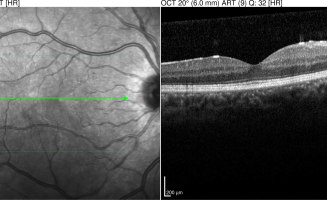

Tomographie en Cohérence Optique (OCT) 2016 et 2018

• 2016 : profil fovéolaire avec peu de remaniement

• 2018 : œdème maculaire cystoïde diabétique avec logettes intrarétinienne, décollement séreux rétinien et exsudats de résorption (points hyper-réflectifs)